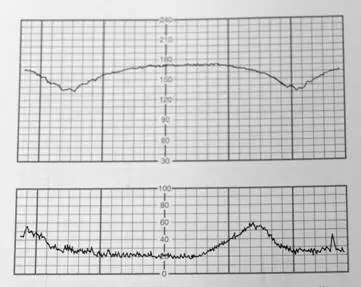

本題圖片為同一 CTG 描記圖(與上題相同):

- 上 panel(FHR 曲線):基礎心率約 150 bpm,可見兩次平滑、緩慢的減速,減速 nadir 落後於宮縮波峰,呈現 late deceleration 型態。

- 下 panel(宮縮曲線):兩次規律宮縮,波峰清晰,FHR 的最低點均出現在宮縮峰值消退後,確認為 late deceleration。

- 圖形特點:波形平滑、減速幅度適中(約 15–20 bpm)、對稱緩降緩升,無急速下降(排除 variable)、無正弦波形(排除 sinusoidal)、時間滯後明顯(排除 early)。